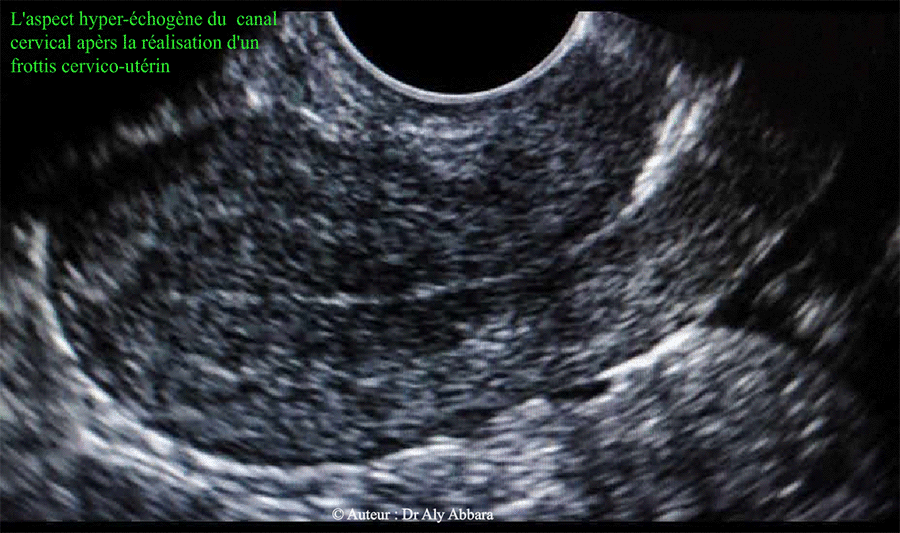

L'aspect hyper-échogène du canal cervical après la réalisation d'un frottis cervico-utérin par la rétention de particules d'air par la brosse

• Images échographiques montrant l'aspect échographique du canal cervical après la réalisation d'un frottis cervico-utérin (FCU).

Cette hyperéchogéncité manifeste est due à la présence de particules d'air déposées dans le canal cervical lors de l'introduction de la brosse ou la tige-coton afin d'effectuer le frottis endocervical.